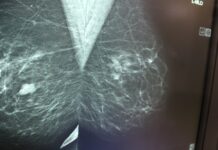

Miesiąc różowej wstążki, czyli mamo, siostro, żono zbadaj się.

Miesiąc profilaktyki wczesnego wykrywania raka pierwsi trwa. Październik miesiącem różowej wstążki, czyli promowania i badań diagnostycznych i zachęcania pań w różnym wieku do badania...